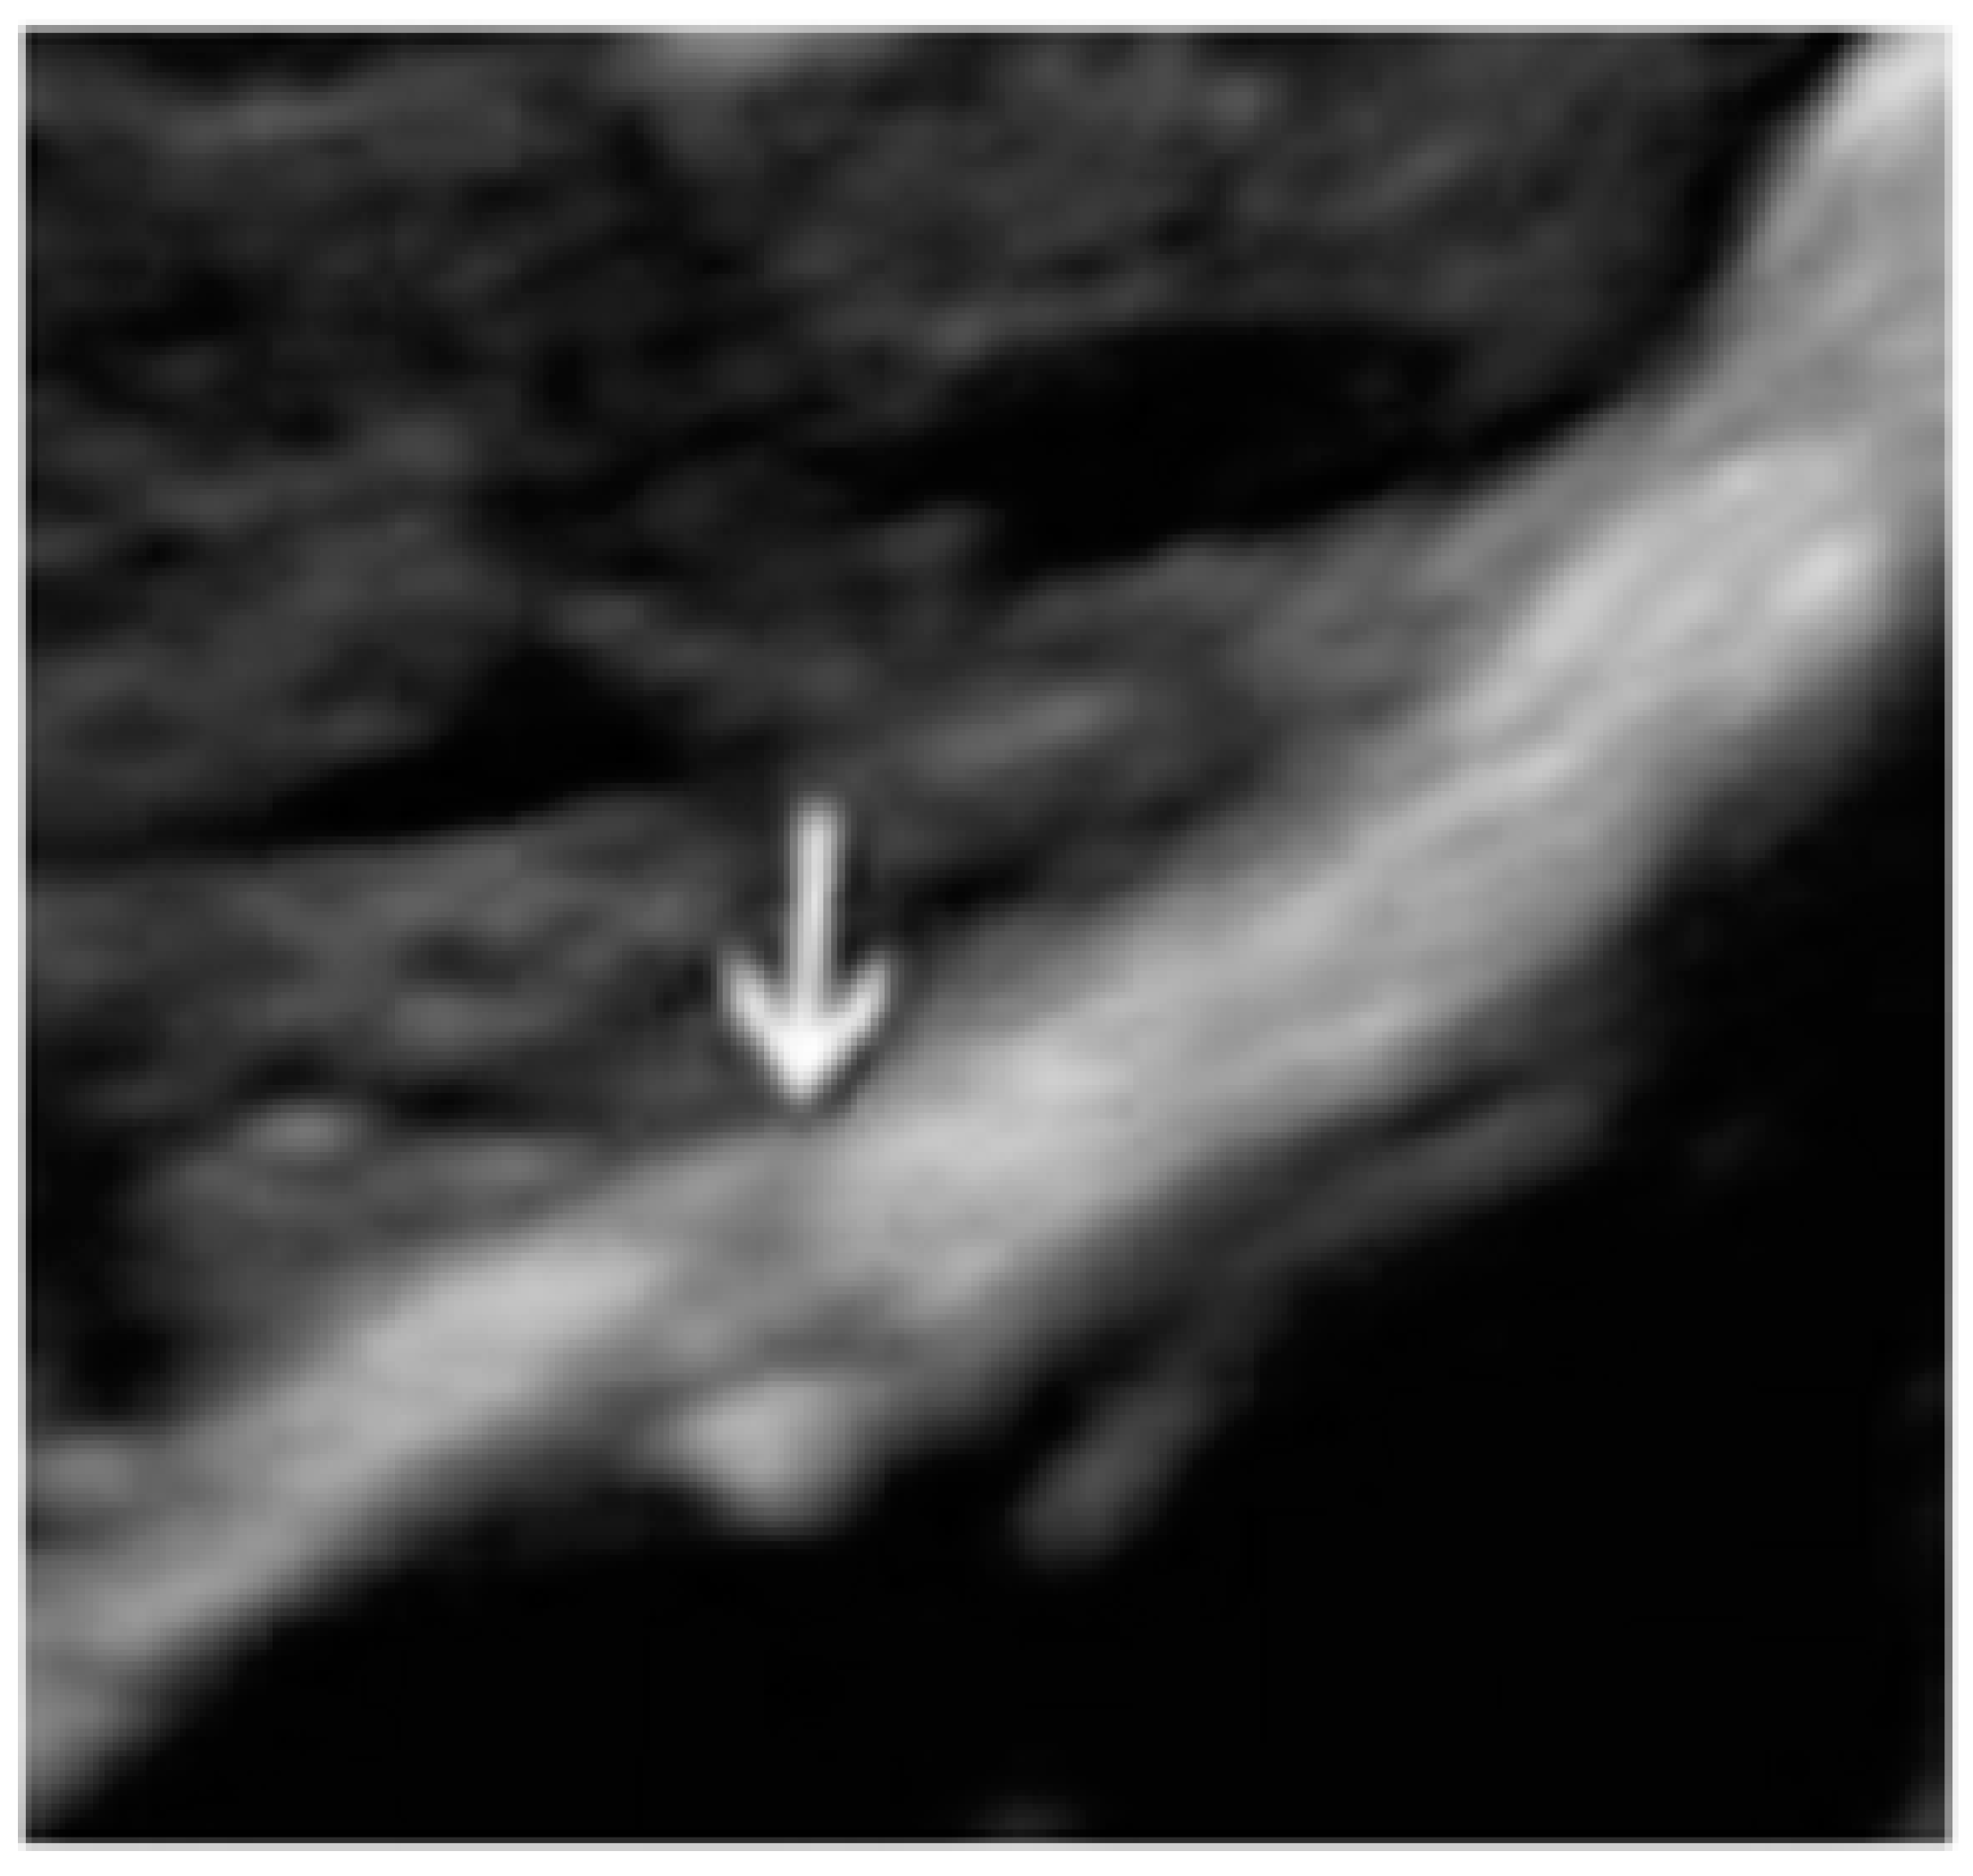

- The presence of hypoechogenic associated tissue (hypoechoic areas surrounding a small cyst area; we called this a “hat”). This tissue does not protrude or invaginate the peritoneal surface.

3.1. Cystic Solitary Lesion